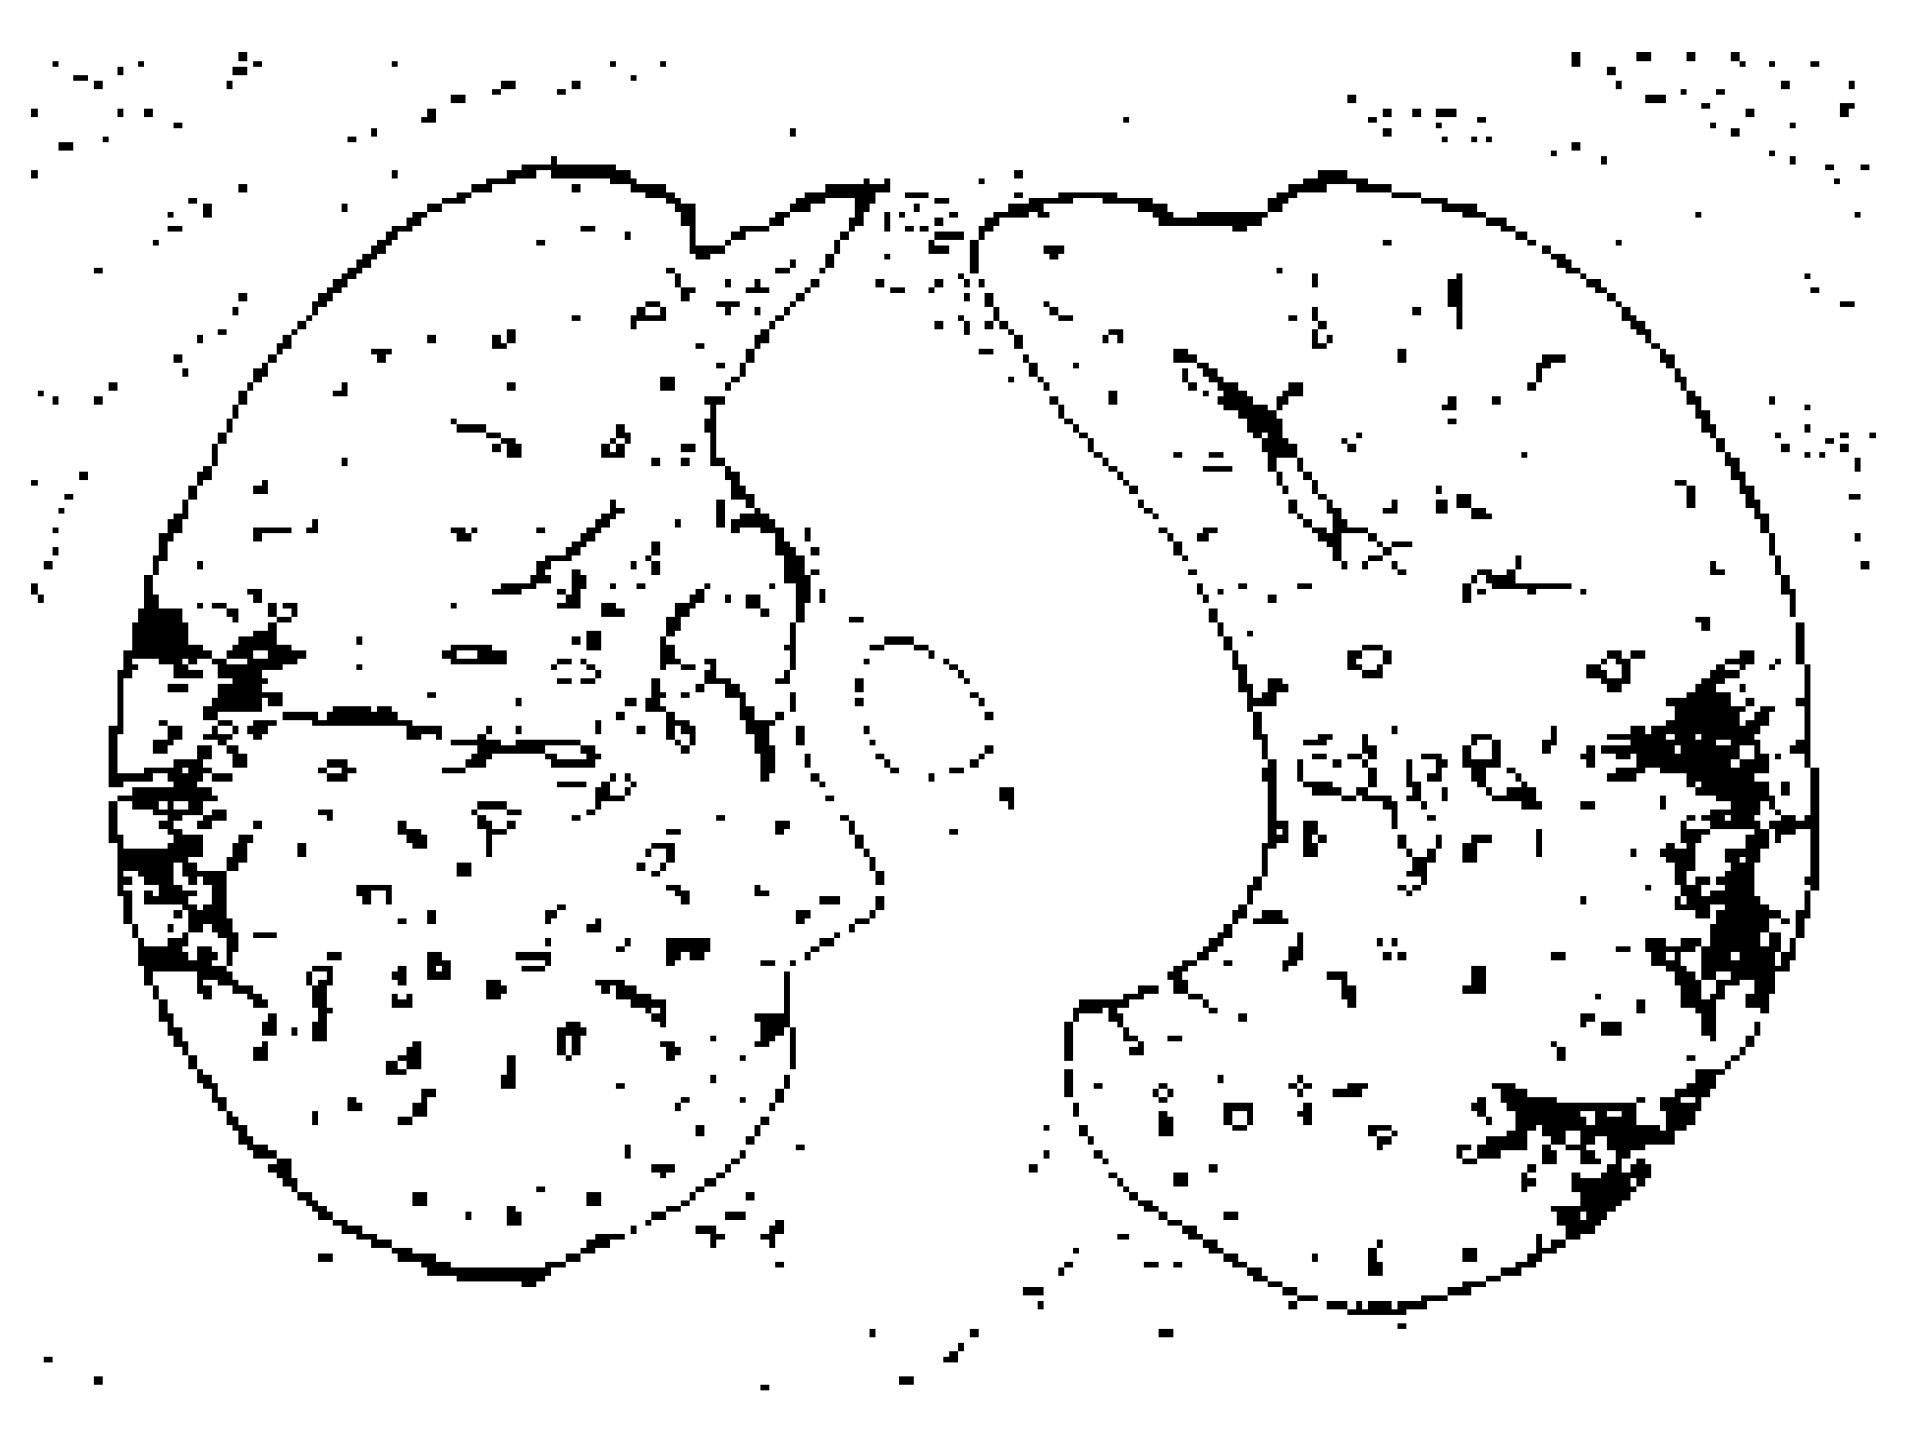

To generate the most effective training results, the input data was pre-processed with various methods [20]. The approach involved converting grayscale input images into binary images using fuzzy logic to isolate ground-glass opacity sections. Grayscale conversion to binary images presented a variation of results. To extract meaningful features from the training set, fuzzy logic edge detection was used on a binary image that was created from a grayscale image filter using adaptive thresholding. Figure 2 shows a COVID scan in binary format. The aim was to analyze the GGO and consolidation areas to form a distinct differentiation between COVID and non-COVID scans. The consensus is that COVID scans display patterns of white pixels (1′s) in binary form, whereas non-COVID scans will display minimal white pixels or none. Figure 3 shows inverted versions of the source image where the black pixels are the isolated consolidation sections [21]. Figure 4 is an example of a COVID image that is filtered to display the most important parts of the image. The white patches on the edges are the detections of GGO presence. By using the grayscale thresholding function, the values were calculated within the range ‘i’ as shown by the expression (95 < i < 145).

Figure 4. Binary image after using a median filter kernel size 10 × 10.